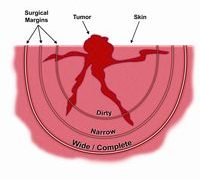

眼の疾患  腫瘍

腫瘍  腫瘍

腫瘍  腫瘍

腫瘍  腫瘍

腫瘍  腫瘍